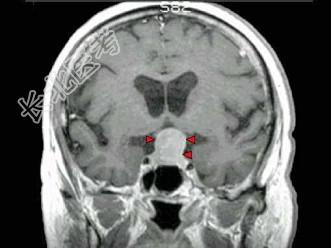

- 单项选择题男,37岁, 视力模糊,部分视野缺失, 伴有头痛、恶心数月,MRI检查如图, 最可能的诊断为 ( )

A、颅咽管瘤

B、脑膜瘤

C、蛛网膜囊肿

D、垂体瘤

E、表皮样囊肿